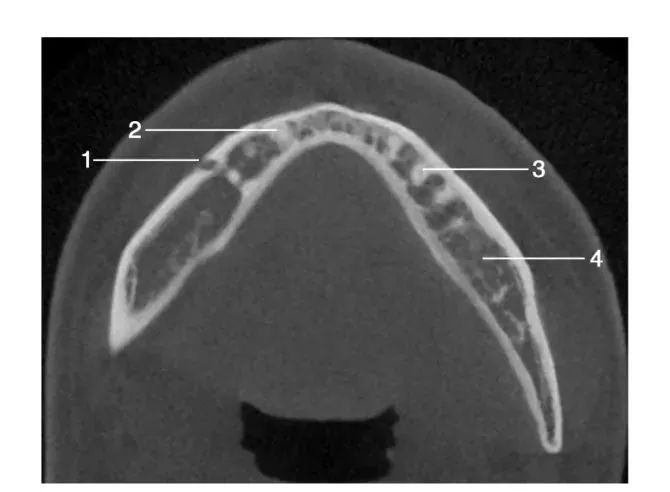

1、水平位影像经下颌体颏孔区层面水平位图像1.颏孔 ; 2.右下尖牙牙根; 3.左下第一前磨牙牙根; 4.下颌体

经下颌后牙牙冠处层面水平位图像